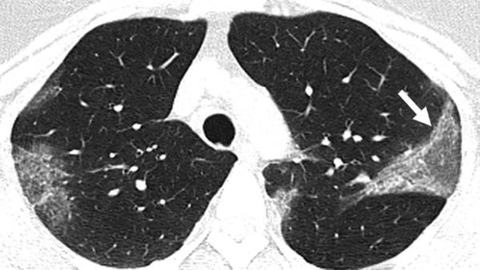

Hình ảnh tổn thương phổi đặc trưng của các bệnh nhân nhiễm Covid-19

Khi mất đi lớp bảo vệ, đường hô hấp sẽ bị chất bẩn, dịch lỏng và virus tràn ngập. Cách thức tấn công này khiến nhiều bệnh nhân Covid-19 bị viêm cả 2 lá phổi.